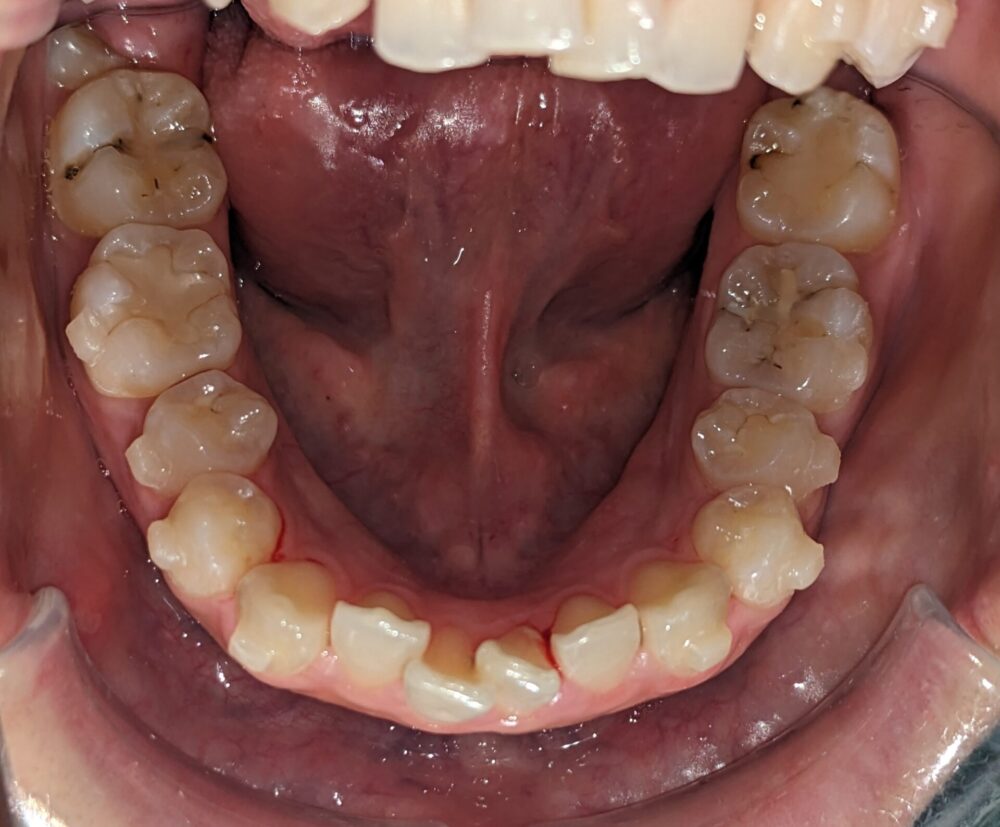

- 主訴

- 前歯が気になる(上下)

- 診断名あるいは主な症状

- 叢生

- 年齢

- 22才

- 治療に用いた主な装置

- マウスピース

- 抜歯部位/抜歯有無

- 無し

- 治療期間

- 約半年

- 総費用

- ¥840,000

- 主なリスク・副作用

- 歯肉退縮,歯根吸収,疼痛,咬合の違和感,装置の違和感,虫歯,歯肉炎